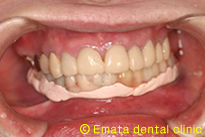

![]() |

合わない入れ歯 |

顎の骨の形態から入れ歯はむずかしそうですね。 |